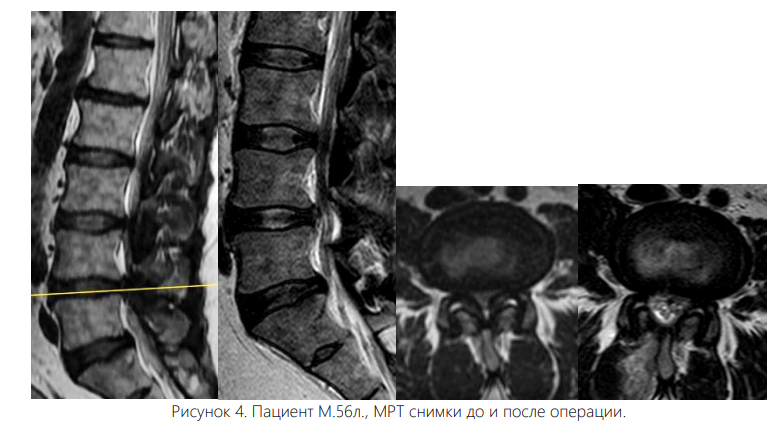

Вмешательство осуществляли под интубационным наркозом. Все операции были выполнены одним и тем же хирургом. Пациента укладывали на живот с подложенными мягкими валиками под грудной клеткой и тазом, уменьшая таким образом внутрибрюшное давление и степень интраоперационного кровотечения. Уровень вмешательства определяли с помощью интраоперационных флюороскопии. Срединный кожный разрез длиной 0,7 см располагался точно над уровнем соответствующего межпозвонкового диска. Зона ламинотомии в краниальном направлении простиралась до области прикрепления желтой связки к дуге вышележащего позвонка, а каудально резекция дуги нижележащего позвонка составляла не более 2-3 мм для адекватного обнажения ножки позвонка. Проведен анализ результатов хирургического лечения 102 больных со стенозом поясничного отдела позвоночника, находившихся в отделении вертебрологии Республиканском центре травматологии и ортопедии Узбекистана в период с 2020 по 2024 год. Для определения размера позвоночного канала, а также степени дегенеративного стеноза в позвоночный канал всем больным была выполнена рентгенография, МСКТ, МРТ. Возраст больных от 44 до 84 лет, мужчин – 46%, женщин – 54%. Всем пациентам была произведена операция - эндоскопическая декомпрессия методом PSLD (Posterior Spinal Lumbar Decompression). На одном уровне (44 больных) и (32 больных) – на двух уровнях, 18-больных в трех уровнях, 8-больных в четырех уровнях.